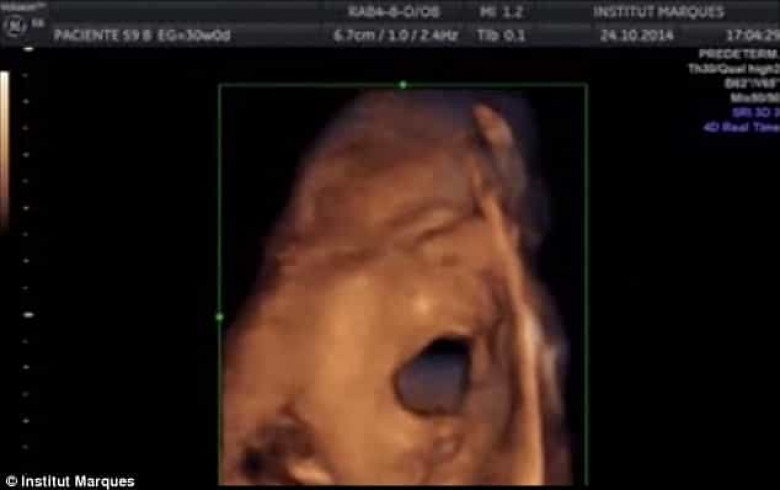

Ինչպես նշում է The Daily Mail-ը, Բարսելոնայի Մարկեսի անվան համալսարանի գիտական թիմն ապացուցել է, որ պտուղն ունակ է ոչ միայն լսել ձայները, այլև` դիմախաղով ու բերանի շարժումներով արձագանքել դրան։ Ըստ մասնագետների՝ պտղի նման պահվածքը ենթադրում է, որ նա «երգում» է։